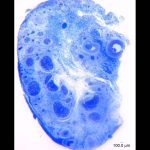

人間のクリトリスの神経線維をガチで数えた研究「1万本以上あった」 – ナゾロジー

https://nazology.kusuguru.co.jp/archives/117010

レス1番のリンク先のサムネイル画像